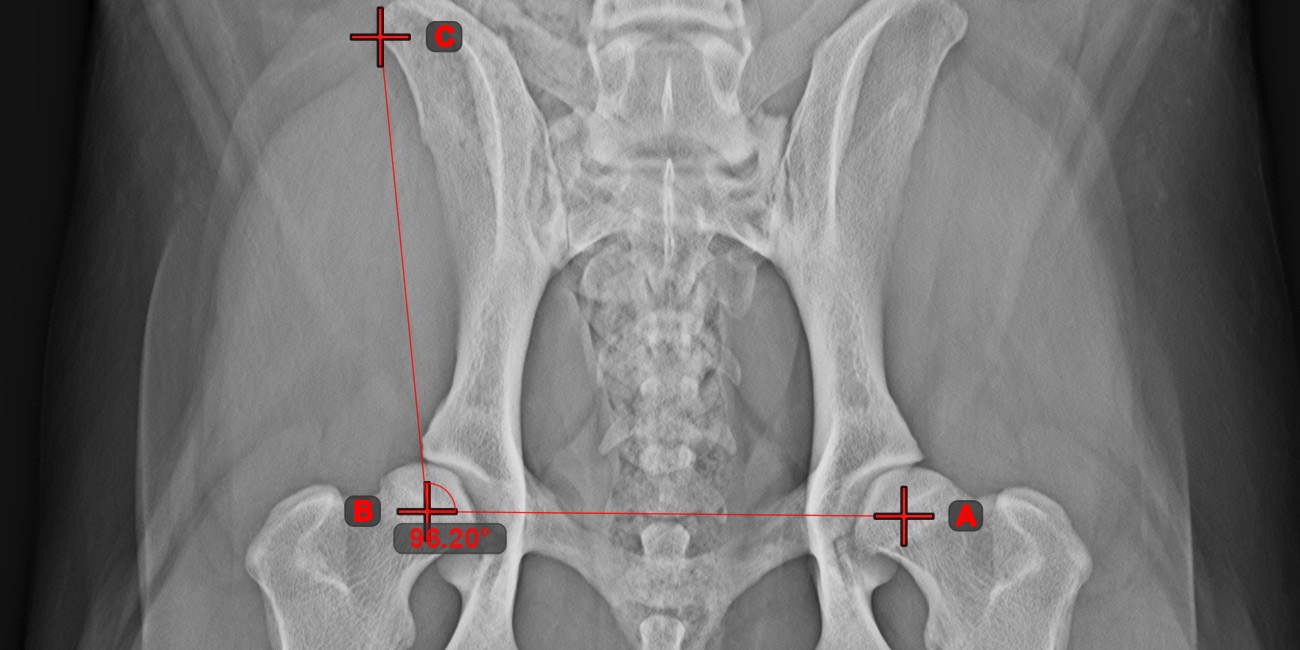

Angle of Lines¶

Select the tool from the left toolbar and assign it to one of the available mouse buttons. Start by selecting the first line from the ones already drawn on the scene, or place the start and end points to create the line. Follow the same steps for the second line of the measurement. The angle between the two lines will be automatically calculated.

Modify the start and end points of both lines by using the Select/Move Item tool. The angle between the two lines will be automatically recalculated.

Information

If two lines do not intersect directly, the angle of their extended projections on the scene will be calculated.